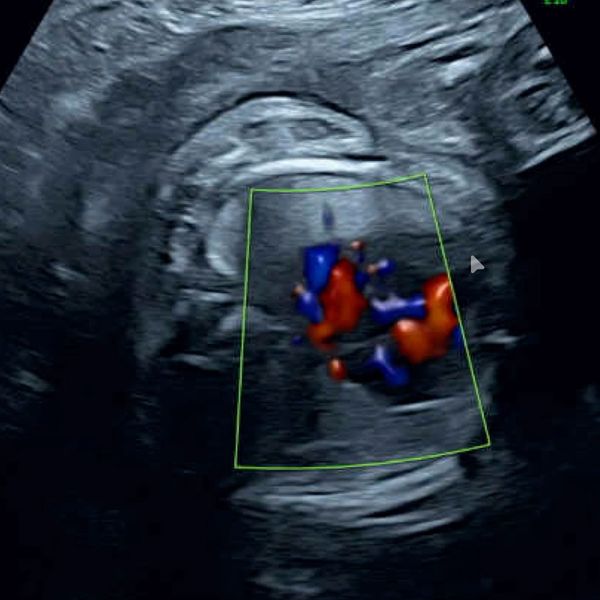

A fetal echocardiogram is also obtained often to obtain a measurement as to how hard the heart is working, called combined cardiac output (CCO), as well as other signs that the heart is under strain.

(Pic: Echocardiogram of a fetus with large SCT)